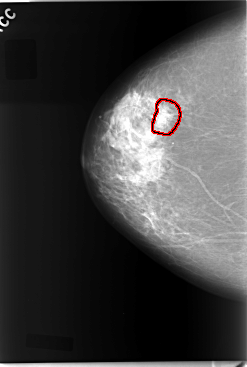

C_0045_1.RIGHT_CC

FILE: C_0045_1.RIGHT_CC.OVERLAY

TOTAL_ABNORMALITIES 1

ABNORMALITY 1

LESION_TYPE CALCIFICATION TYPE PLEOMORPHIC DISTRIBUTION CLUSTERED

ASSESSMENT 5

SUBTLETY 4

PATHOLOGY MALIGNANT

TOTAL_OUTLINES 1

BOUNDARY